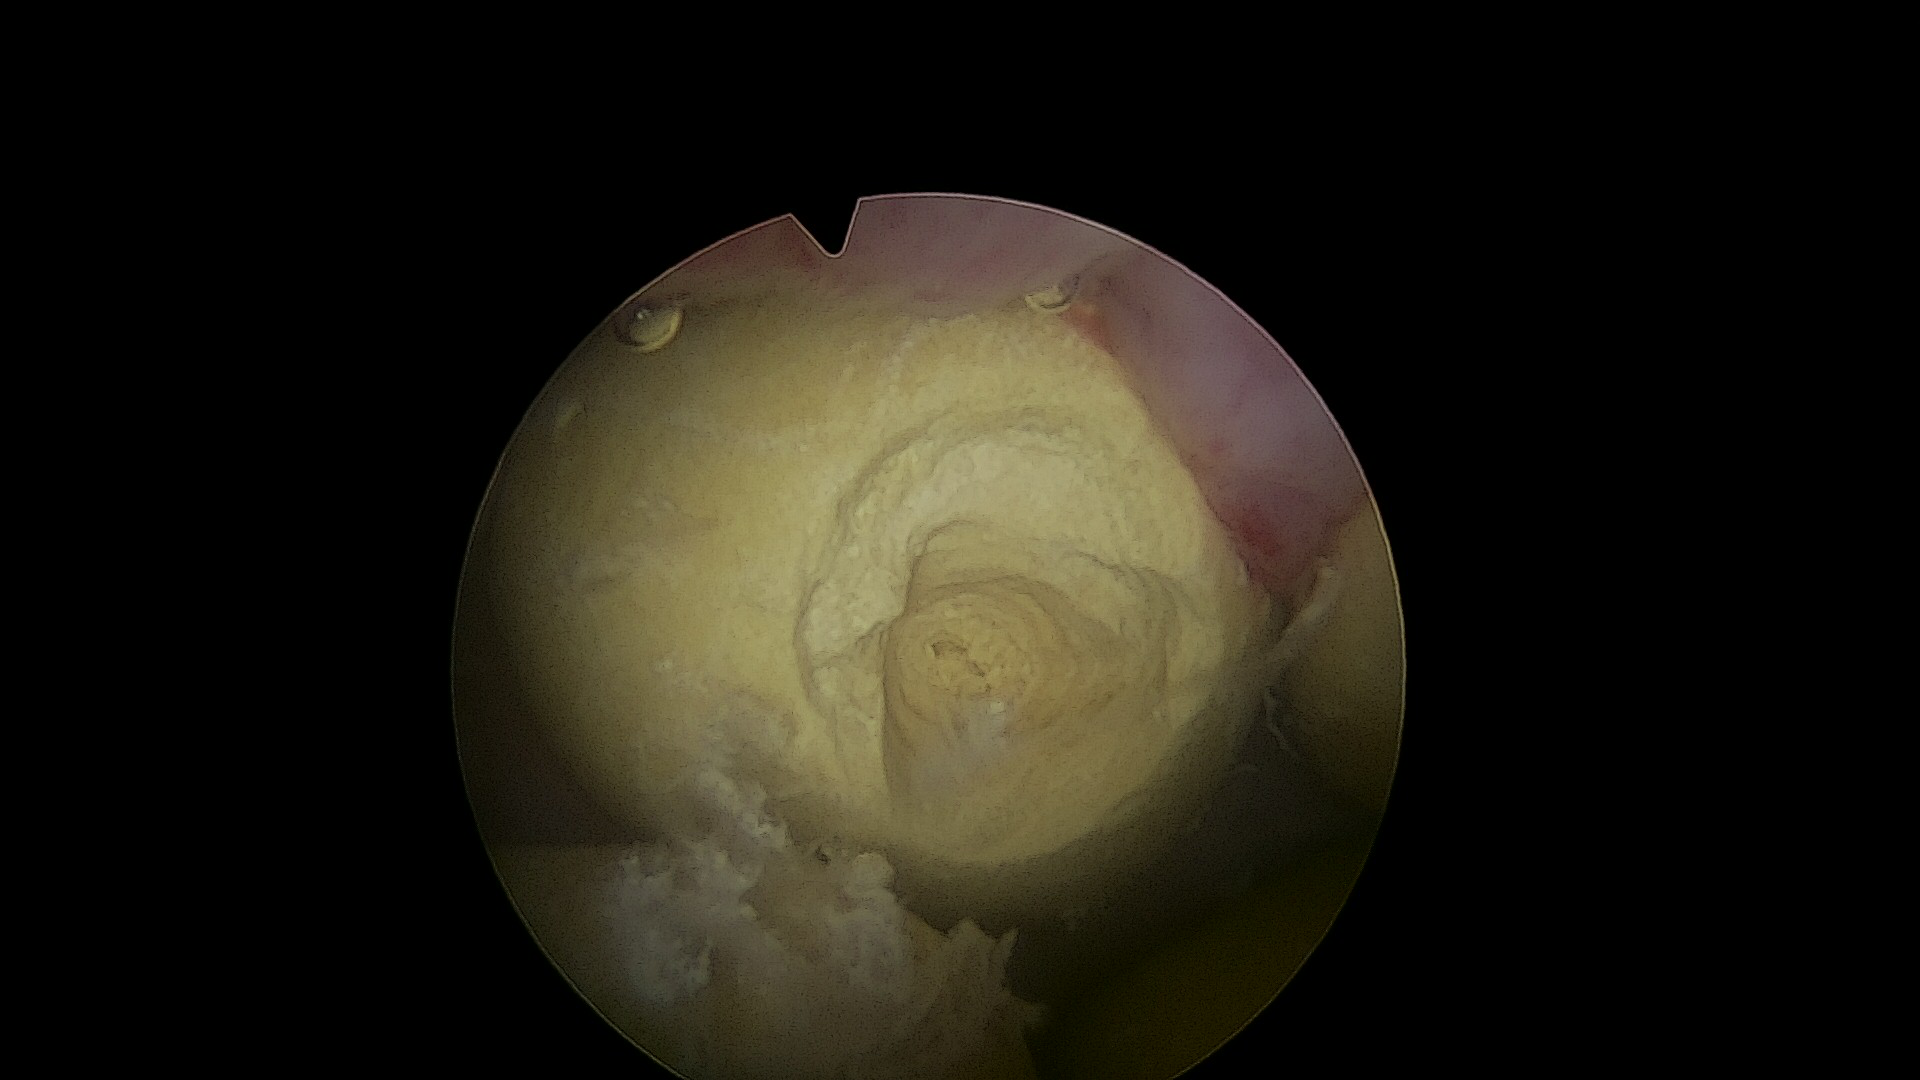

2.前列腺汽化电切设备

前列腺汽化电切术 术前术后后对比